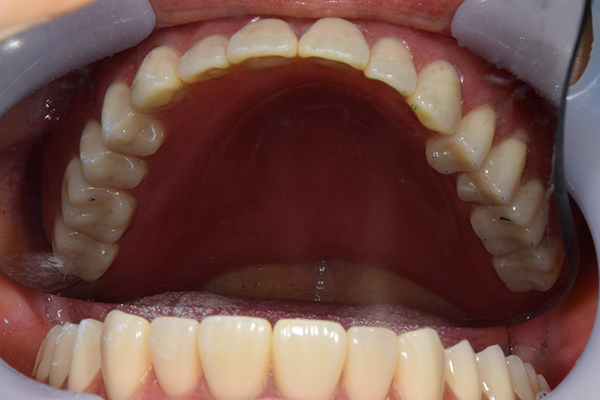

ケース1(自費の部分入れ歯)

前歯が折れて当院にいらっしゃいました。 過去に下の入れ歯を作ったが、合わなくなってずっと入れ歯をいれていらっしゃらない患者様でした。 これは奥歯で噛むことができないため、前歯で噛むことを繰り返したために、負担に耐えられなくなった前歯が折れてかぶせ物ごと 外れてしまったのだと考えられます。 痛くない、違和感の少ない、下の入れ歯を作ることがこの方のゴールであると考えられました。

シリコンで精密な型取りを行いました。

噛み合わせチェックです。 奥歯でしっかりものが噛める様に高さを決めていきました。

金属を使用して、薄く違和感が少ない入れ歯が完成しました。 また、見た目にも気を使い、バネが見えにくい様な構造にしました。

入れ歯をお口の中にいれた状態です。前歯もMTMといって、歯を少し引っ張り出す処置を行なったことで、しっかり残せて、またかぶせ物をしました。

年齢 70歳・女性

主訴 前歯が取れた

治療期間 8ヶ月

治療費 .MTM:110,000円

.ファイバーコア:16,500円

.E-maxクラウン:110,000円

.義歯:660,000円

治療方針 長年使ってきた義歯の人工歯が磨耗し、臼歯部での咬合がすくなくなり、前歯部での接触が強くなったことで生じた前歯の破折なので、義歯も作り変える必要がある。

治療内容 前歯部MTMと同時に審美面の回復。

MTM中に義歯の作成も同時に行う。

最終的に義歯と前歯のクラウンを同時にいれる。

義歯は下顎で、しっかり噛めること、違和感の少ないものという希望があったため、なるべく入れ歯を薄く作成するために金属をしようした義歯とした。

また、見た目もあまり義歯が目立たない様に、バネの部分を見えにくいように作成した。

特記事項 歯にもともと入っていた金属の種類によっては、歯自体の変色を治療で変えられないこともある。 義歯は作ってから痛みがでることがありますが、それは調整を行うことで痛くなくすることができます。